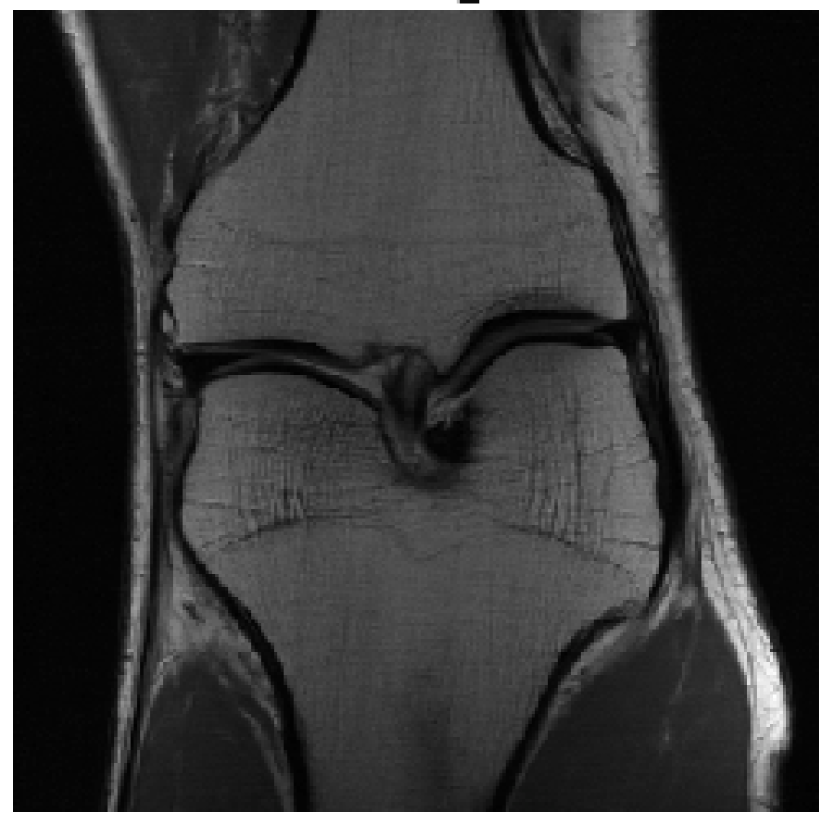

We evaluated our models on three data sets: the validation set as in Zbontar et al. (2018), and the test and challenge sets through the fastMRI website. A summary of these evaluations can be found in table 1111Results on the challenge data set will be added once publicly available.. To assess image quality more closely, we show some exemplary reconstructions from each model in figure 1.

(c) Multi-Coil 8-Fold

Reconstruction

Refer to caption

Figure 1: Example reconstructions. The reconstructions visually improve the ground truth images, suggesting a strong prior.